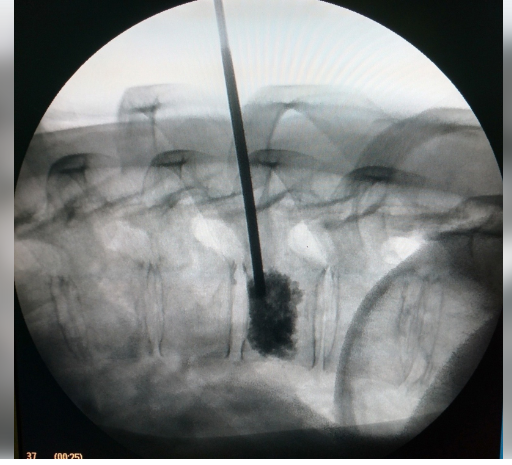

Женщина 45-лет поступила в больницу с жалобами на жгучие боли в грудном отделе позвоночника, беспокоящие на протяжении последних десяти лет. Из анамнеза известно, что пациентка обследовалась амбулаторно, выполнила МРТ грудного отдела, на котором выявилась гемангиома Th9 позвонка. При обращении к врачам по месту жительства в оперативном лечении было отказано. В больнице женщину осмотрел врач-нейрохирург, было принято решение об оперативном лечении. В марте этого года женщину прооперировали — сделали транскутанную вертебропластику Th9 позвонка костным цементом. Операция проводилась под местной анестезией в течение 25 минут нейрохирургом Арсланом Асылбаевым. Через час после операции пациентка была вертикализирована, сразу после операции отмечено отсутствие болей в грудном отделе, которые мучали её на протяжении последних десяти лет. Женщину выписали на вторые сутки после операции.

В больнице женщину осмотрел врач-нейрохирург, было принято решение об оперативном лечении. В марте этого года женщину прооперировали — сделали транскутанную вертебропластику Th9 позвонка костным цементом. Операция проводилась под местной анестезией в течение 25 минут нейрохирургом Арсланом Асылбаевым. Через час после операции пациентка была вертикализирована, сразу после операции отмечено отсутствие болей в грудном отделе, которые мучали её на протяжении последних десяти лет. Женщину выписали на вторые сутки после операции.